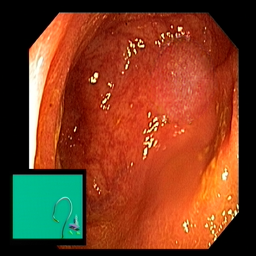

(a) Refer to caption Refer to caption Refer to caption Refer to caption Refer to caption Refer to caption

(b) Refer to caption Refer to caption Refer to caption Refer to caption Refer to caption Refer to caption

(c) Refer to caption Refer to caption Refer to caption Refer to caption Refer to caption Refer to caption

(d) Refer to caption Refer to caption Refer to caption Refer to caption Refer to caption Refer to caption

(e) Refer to caption Refer to caption Refer to caption Refer to caption Refer to caption Refer to caption

(f) Refer to caption Refer to caption Refer to caption Refer to caption Refer to caption Refer to caption

(g) Refer to caption Refer to caption Refer to caption Refer to caption Refer to caption Refer to caption

(h) Refer to caption Refer to caption Refer to caption Refer to caption Refer to caption Refer to caption

Figure 3: Sample data used and generated in the different steps of PolypConnect pipeline. (a) - real polyp images, (b) - manually annotated polyp masks, (c) - randomly selected colon images used as input to the final step of PolypConnect, (d) - extracted edge images of row c. (e) - extracted edge images of polyp regions of row a using the masks of row b. (f) - combined edge images of row d and f. (g) - generated polyp on the images of row c using EdgeConnect. (h) - generated samples from AOTGAN.